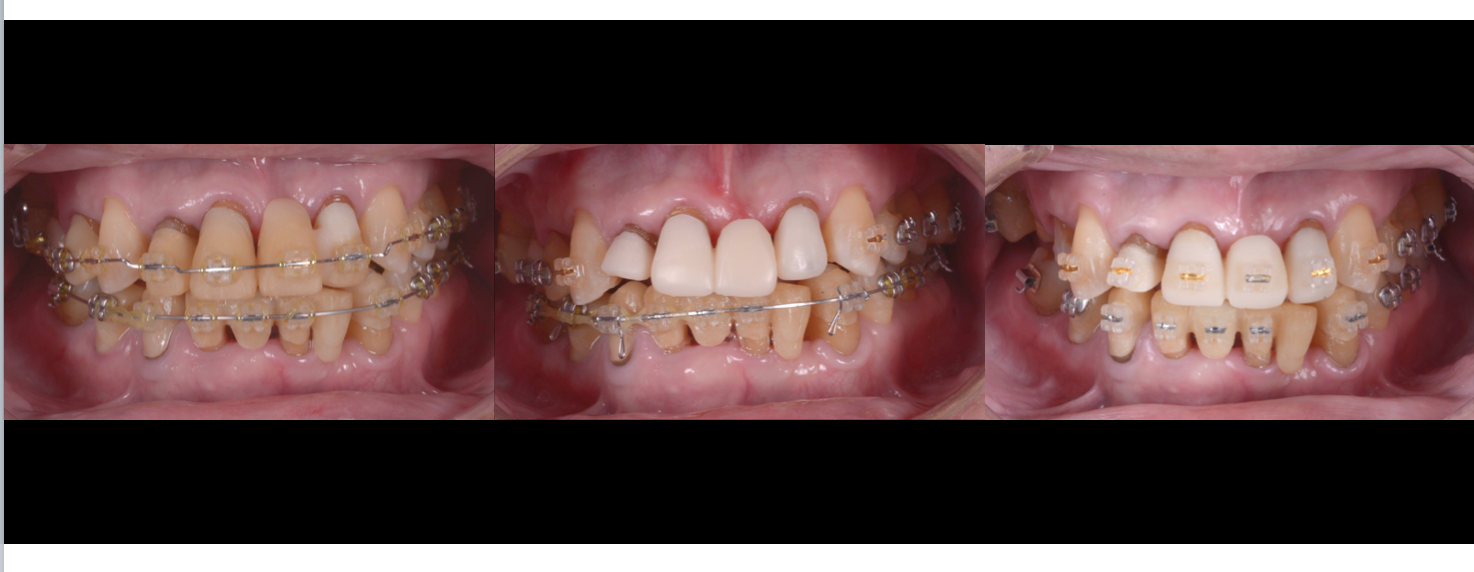

↑個々の歯の生えている向きに合わせて仮歯を装着しました。治療前は無理やり歯並びの悪い状態に被せ物が入っていましたが、どうですか?こうしてみるとかなり前歯を中心に個々の歯の向きが様々なのが理解できると思います。

これが今現在の歯の生えている向きで、これを矯正治療で正しい位置と向きに改善します。

様々な向きの歯に仮歯を入れた状態で型を取り模型を作成し、全ての歯を分割しどうしたら理想的な並びになるか設計図を矯正医と歯科技工士と共に作成します。

そして矯正治療の開始です。矯正治療期間は約3年かかりました。

ほぼ術前の設計図通りの位置にはを並べることができたでしょうか。